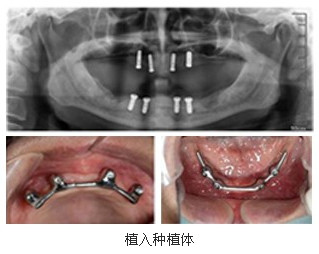

病例3   重度牙周病导致缺牙,种植义齿修复